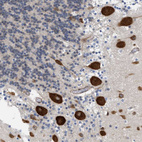

Immunohistochemistry analysis in human cerebral cortex and duodenum tissues using HPA017438 antibody. Corresponding GPRASP2 RNA-seq data are presented for the same tissues.